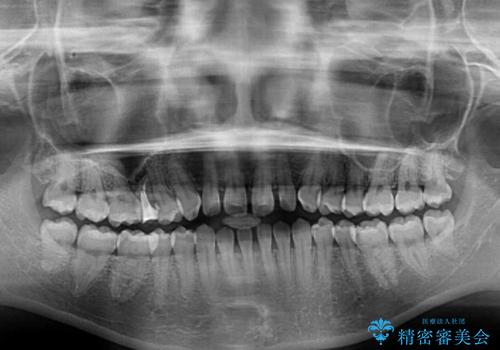

- 前歯の上下スペースと前歯の隙間を気にして来院された患者様です。

飲み込みや話をするときに舌を突出させる癖が強くあり、それが原因でスペースが空いていました。